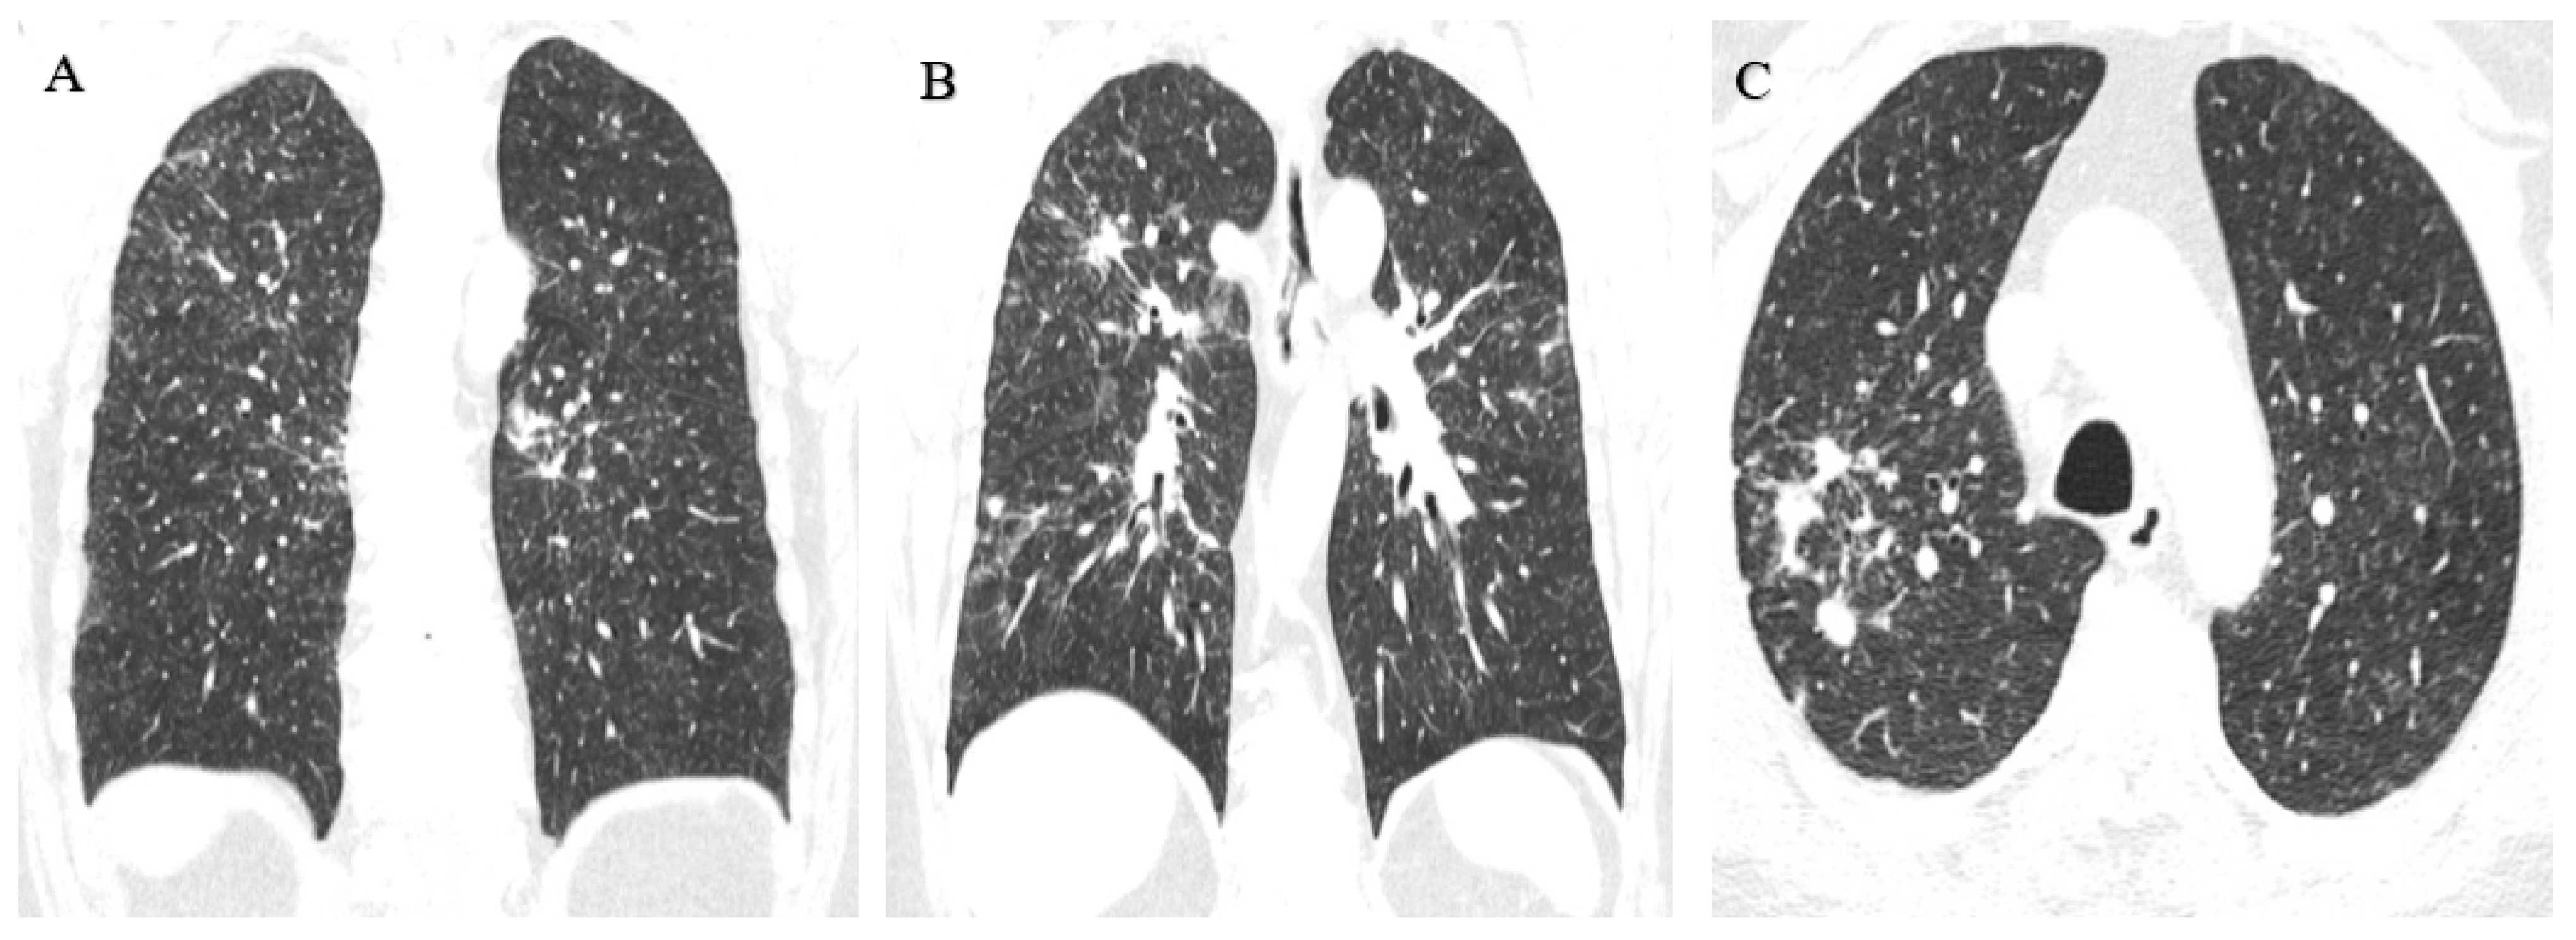

3.1.2. Case 2